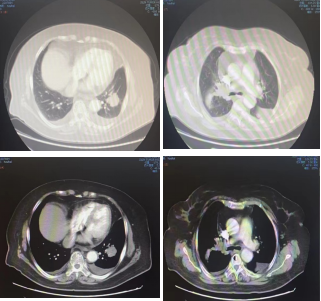

影像学-增强CT检查:右肺上叶中心型肺癌伴阻塞性肺炎,左肺下叶占位性病变,长径:2.9cm;纵隔及双肺门淋巴结转移,较大位于7组,短径1.1cm,肝脏多发点状异常密度影,考虑转移,多发骨转移。

CT检查——基线

影像学-增强CT检查:治疗4周期后,病灶缩小31%,疗效评估为PR。

靶病灶:左肺病灶明显缩小;

非靶病灶:右肺门病变缩小。

CT检查——治疗4周期后